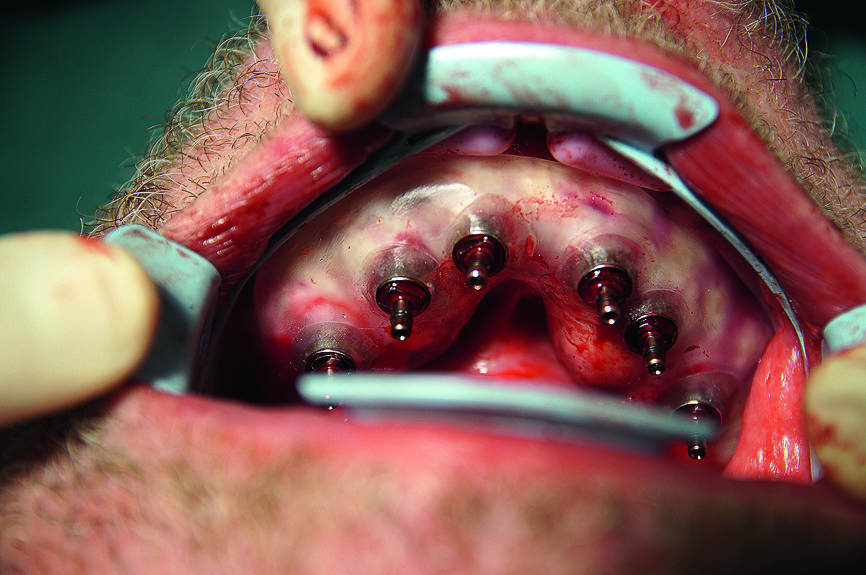

Fig. 18 : Tous les implants CAMLOG guidés dans la mandibule.

19 : Résultat de l’implantation avec tous les implants in situ.

Dans la mandibule, la muqueuse a été perforée avec un emporte-pièce rotatif au niveau des sites dentaires 36, 34, 32, 42, 44 et 46 (Fig. 14). Après le retrait du gabarit, les endroits de la gencive marques a l’aide de l’emporte-pièce ont été incises davantage et les bouchons de gencive découpée éliminés, afin d’obtenir une mandibule perforée et préparée (Fig. 15). Ensuite, le gabarit de forage a été remis en place. Des forêts à cannelures droites (foret-guide de 6 mm ; forets de mise en forme de 9, 11 et 13 mm) ont été utilisés pour préparer les ostéotomies implantaires au niveau des sites dentaires 36, 34, 32, 42, 44 et 46, conformément aux instructions du fabricant (Fig. 16).

L’insertion des implants a été réalisée à l’aide de la clé à cliquet DRM et de la douille standard, avec un couple de serrage d’environ 35–45 Ncm, afin de parvenir à une stabilité primaire maximale (Fig. 17). Par la suite, les tenons pour navigation implantaire et le guide chirurgical ont été retirés du maxillaire pour y insérer les façonneurs gingivaux, avec un couple de serrage de 25 Ncm (Figs. 18 et 19). Une technique similaire a été utilisée pour la préparation des lits implantaires et l’insertion des implants dans la mandibule, ou six implants CAMLOG de 4,3 mm in diamètre et de 11,0 mm de longueur ont été insérés sous guidage total dans les sites dentaires 15, 14, 12, 22, 24 et 25. Une tomographie panoramique dentaire postopératoire a permis de visualiser les implants insérés dans le maxillaire et la mandibule (Fig. 20).